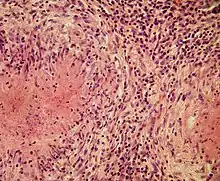

Structurally, epithelioid cells (when examined by light microscopy after stained with hematoxylin and eosin), are elongated, with finely granular, pale eosinophilic (pink) cytoplasm, and central, ovoid nuclei (oval or elongate), which are less dense than that of a lymphocyte.[4] They have indistinct shape and often appear to merge into one another, forming aggregates known as giant cells. When examined by transmission electron microscopy in epithelioid cells in the field of Golgi lamellar complex are taped not only zonated, but also sleek vesicles with dense center, and also great many (more than 100) large granulas with diameters up to 340 nm and with finegranular matrix more light than in macrophage granulas, sometimes with perigranular halo. “The most prominent feature of these cells is the enormous Golgi area; up to 6 individual stacks of Golgi cisternae may be present as well as a few bristle-coated and numerous smooth vesicles”.[5][4] Epithelioid cells have tightly interdigitated cell membranes in zipper-like arrays that link adjacent cells.[3] This cells are central in the formation of granulomas, which are associated with many serious diseases.[4] In granulomas, epithelioid cells perform the functions of delimiting.[3]